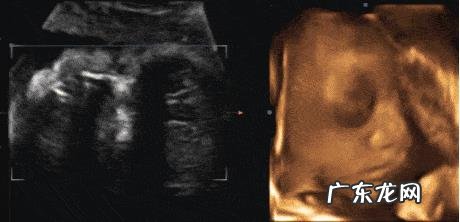

想要排除胎儿是否有先天性心脏病,孕妇怀孕早期可以做NT检查,如果胎儿心脏有异常,能检查出来,在怀孕中期,再做一个心脏B超,看胎儿的心脏是否有缺失,或者是异常 。

如果孕妇年龄大于35岁,染色体有异常,可以直接做羊水穿刺,也可以选择做无创DNA检查 。

孕妇孕期一定要做唐氏儿筛查,NT彩超,唐氏筛查,可以排除胎儿唐氏儿的风险 。